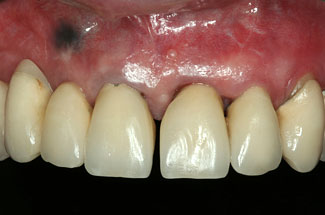

Abbildungen 3-5: Die klinischen Fotographien zeigen den Zustand nach der ersten professionellen Zahnreinigung.

Der komplexe Fall Der komplexe Fall

Abb. 3

Abb. 4